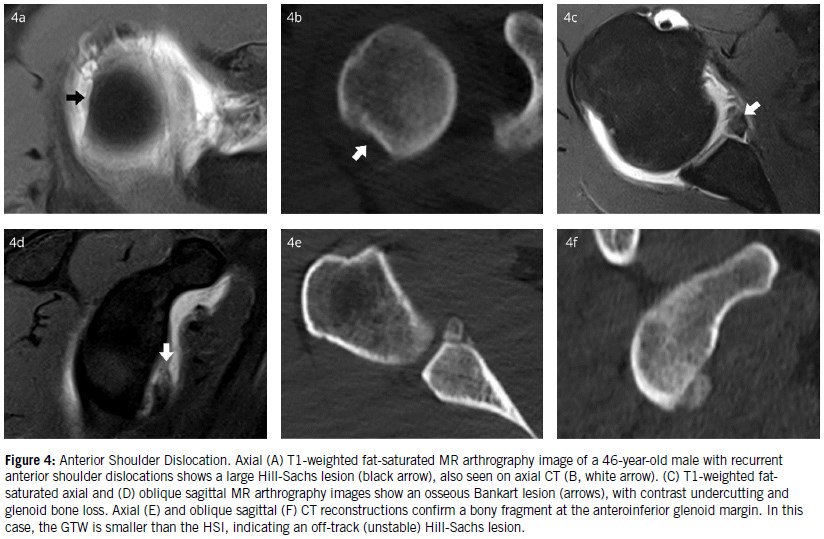

Bankart lesions are the most common labral injuries associated with traumatic anterior instability. These typically involve detachment of the anteroinferior labrum and capsuloligamentous complex, with or without an associated glenoid rim fracture (Figure 4).

Several variants of the Bankart lesion exist (Figure 5):

• GLAD (glenolabral articular disruption): a superficial anteroinferior labral tear associated with adjacent cartilage damage.

• ALPSA (anterior labral periosteal sleeve avulsion): complete detachment with medial displacement and inferior rotation of the labrum. The periosteal stripping occurs, but there is no complete detachment.

• Perthes lesion: an avulsion of the anteroinferior labrum with a medially stripped yet intact periosteum. This lesion is best visualized in the ABER position, which places stress on the anterior band of the IGHL and anteroinferior capsule.

The quantification of traumatic bipolar bone loss in anterior shoulder dislocations using high-resolution CT or MRI has led to the development of the glenoid track concept. This concept defines the glenoid track as the contact zone between the humeral head and the glenoid during shoulder motion from the neutral to ABER position and serves as a valuable tool for estimating the risk of recurrence following anterior shoulder dislocation. Two key parameters used to classify a HSL as on-track or off-track are the glenoid track width (GTW) and the Hill-Sachs interval (HSI). When the GTW is smaller than the HSI, the HSL is considered off-track and therefore unstable. Conversely, if the GTW exceeds the HSI, the lesion is considered on-track and more likely to be stable. This evaluation, combined with the measurement of glenoid bone loss, plays a critical role in guiding appropriate treatment strategies7.